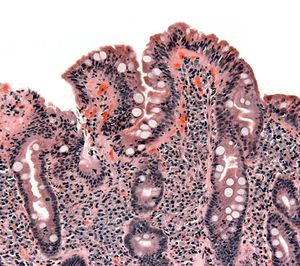

خزعة من الأمعاء الدقيقة تبين الداء البطني ظاهراً بتقصف الخملات، crypt hyperplasia, والخلايات الليمفية تتغلغل في crypts

التنظير العلوي للجهاز الهضمي مع أخذ الخزعات النسيجية هو حجر الأساس في تشخيص داء بطني، يجب الوصول إلى المعي الاثني عشري و المعي الصائم حتى يكون التنظير مجدياً، كثير من الخزعات المأخوذة من مرضى داء بطني قد تبدو سليمة و لذا يجب أخذ عدة عينات نسيجية من مناطق مختلفة حتى يكون التنظير دقيقاً ومثمراً.

تصنيف مارش

يعتمد تصنيف مارش الپاثولوجي لتحديد مدى حدة تأثر الأمعاء الدقيقة بداء بطني، مراحل تصنيف مارش الخمسة هي:

1. المرحلة 0: أغشية مخاطية طبيعية.

2. المرحلة 1: ازدياد عدد الخلايا اللمفاوية في النسيج الطلائي للأمعاء وغالباً ما يكون العدد أكثر من 20 خلية لمفاوية لكل 100 خلية معوية.

3. المرحلة 2: تزايد خبايا ليبركون في جدار الأمعاء.

4. المرحلة 3: ضمور زغابي جزئي أو كلي.

5. المرحلة 4: نقص تنسج البنية المعوية.

عادة ما تتحسن الحالة خلال2-6 أسابيع من إزالة بروتين الگلوتن من الطعام وينصح بإعادة أخذ وفحص الخزعات النسيجية بعد 4-6 شهور من بداية العلاج.